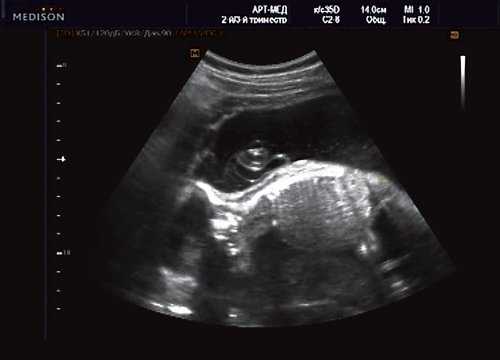

При эхокардиографии изучались четырехкамерный срез сердца плода (рис. 1) и срез через три сосуда (рис. 2). УЗИ проводилось трансабдоминальным датчиком, лишь при необходимости (затрудненная визуализация) использовался внутриполостной датчик. Четырехкамерный срез сердца плода при ультразвуковом сканировании трансабдоминальным датчиком визуализировался в 85% случаев, срез через сосуды - в 73%, при использовании трансвагинального датчика эти цифры существенно возрастали до 100 и 91% соответственно. Оптимизация пренатальной диагностики ВПС может быть достигнута путем строгого соблюдения основных методических правил. При оценке четырехкамерного среза плода необходимо оценить нормальное расположение сердца плода, исключив его эктопию (рис. 3), положение оси сердца плода, что не представляет никаких трудностей, нормальные пропорции и размеры камер сердца, движение створок атриовентрикулярных клапанов должно быть свободным, септальная створка трикуспидального клапана должна располагаться ближе к верхушке сердца (рис. 4). При оценке среза через три сосуда необходимо оценить взаиморасположение сосудов и их диаметр.